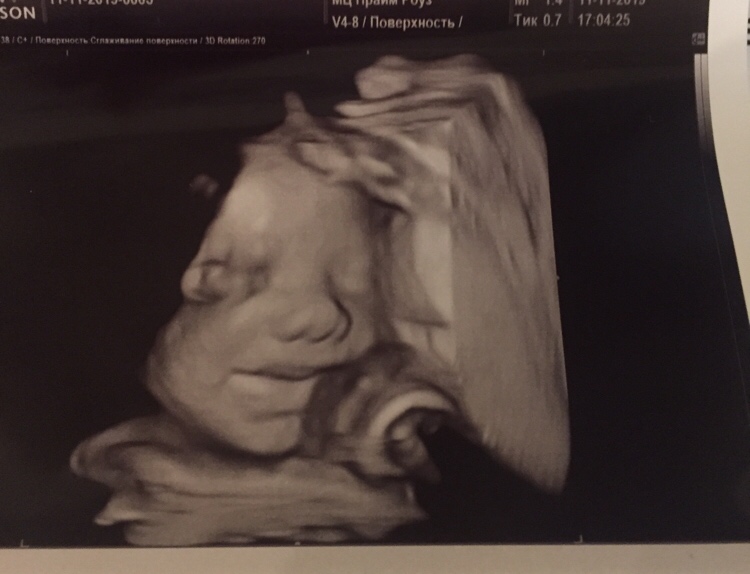

Сегодня была на контрольном узи. Повидались с малышкой, которая сладко улыбалась нам 🥰

Весим 1085 грамм💪

Все хорошо, по размерам в основном опережаем срок чуть-чуть. Кровотоки проверили - тоже в норме. Вот только плацента 1-2 степени. 🤨